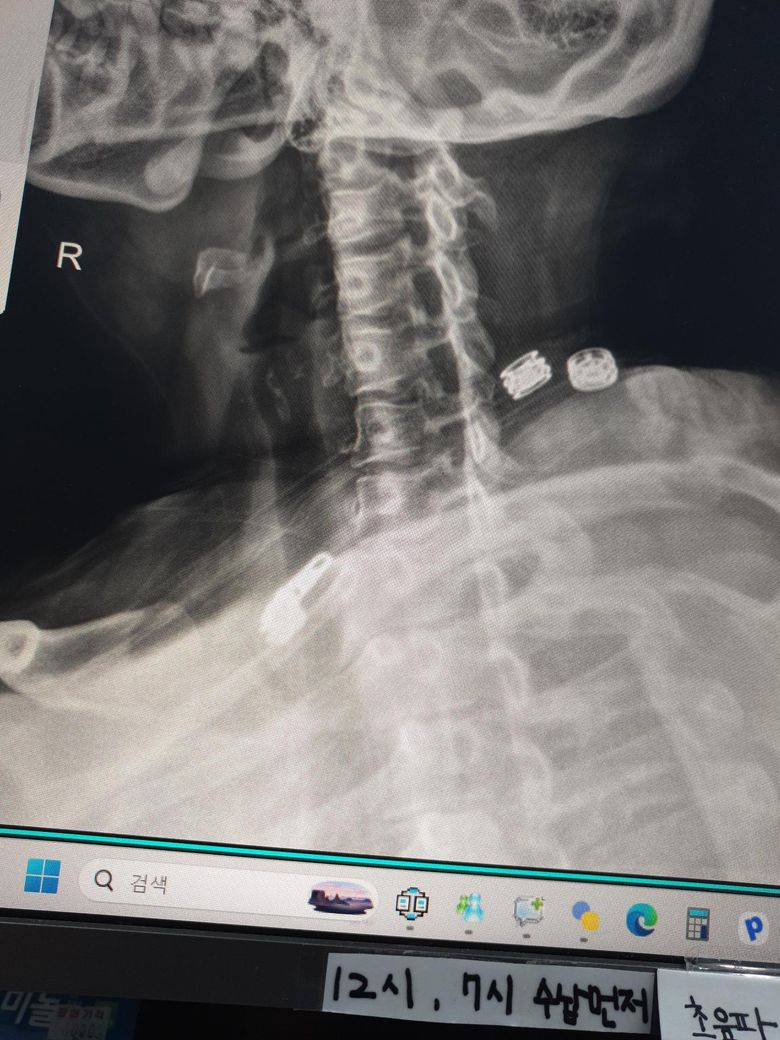

• 1번 째 사진

x-ray 상으로 보았을 때에는 일자목인 것으로 보입니다.

사진상으로 많은걸확인할수는없지만 일자목과함께 약간의 거북목을 가지고있는걸로 보이는데요 이는 굽은등과 평소 자세적인문제등에 의해서 나타날수있습니다~

엑스레이 사진을 보니 일자목 경향이 보이며 이로인해 목 뒤쪽 근육과 후두신경이 계속 긴장해 통증이 발생하는것으로 보입니다. 옆으로 누워 주무시는에 어깨가 말려있다면 어깨 높이를 충분히 받쳐주어 목이 아래로 꺾이지 않도록 유도하는 베개가 필수입니다. 4만원대 예산이라면 메모리폼이나 엘라스틱 소재의 경추형 베개중에서도 양옆이 가운데보다 높은 디자인이 좋습니다. 너무 말랑한것보다는 탄성이 있는 제품이 신경눌림 방지에더 효과적이며, 수건을 말아 목뒤에 받쳐보며 본인에게 맞는 높이를 먼저 테스트해보는것이 좋습니다. 답변이도움됐길 바랍니다!

• 제시된 측면 경추 X-ray를 보면 정상적으로 유지되어야 할 경추 전만(앞쪽으로 휘는 곡선)이 다소 감소되어 보입니다. 이런 경우 후경부 근육 긴장과 후두부 방사통, 말씀하신 신경이 뻗치는 느낌이 흔히 동반됩니다. 베개 선택이 증상에 직접적인 영향을 줄 수 있는 상태입니다.

핵심은 “높은 베개”가 아니라 “경추를 받쳐주는 구조”입니다. 현재처럼 어깨가 말리고 옆으로 주로 주무시는 경우라면 단순히 낮은 베개는 오히려 기도를 좁히고 근육 긴장을 악화시킬 수 있습니다.

옆으로 잘 때 기준으로는 어깨 두께를 채워서 머리와 척추가 일직선이 되도록 해야 합니다. 일반적으로 성인 여성 기준 압축 후 높이가 약 8에서 12cm 범위가 적절한 경우가 많습니다. 다만 중요한 것은 중앙이 꺼지는 형태가 아니라, 목을 받치는 부분이 살짝 더 높은 “경추 지지형” 구조입니다. 메모리폼이 무난하며 너무 푹 꺼지는 제품은 피하는 것이 좋습니다.

뒤로 누웠을 때 기준으로는 목 아래를 받쳐주고 머리는 약간 낮게 위치하는 형태가 이상적입니다. 즉, C자 형태로 경추를 지지해주는 베개가 적합합니다. 이런 구조가 없으면 현재처럼 후두부 통증이 지속될 수 있습니다.

정리하면, 옆으로 잘 때는 어깨 높이를 채우는 충분한 높이, 동시에 목을 따로 지지하는 경추 지지 구조, 너무 부드럽지 않은 소재가 기준입니다. 가격대 4만원이면 경추 지지형 메모리폼 제품 충분히 선택 가능합니다.

추가로, 통증이 가만히 있어도 지속되고 후두부에서 방사되는 양상이라면 단순 근육 문제 외에 후두신경통 가능성도 있습니다. 베개 교체 후에도 1주에서 2주 내 호전이 없으면 물리치료나 신경차단술 평가가 필요할 수 있습니다.